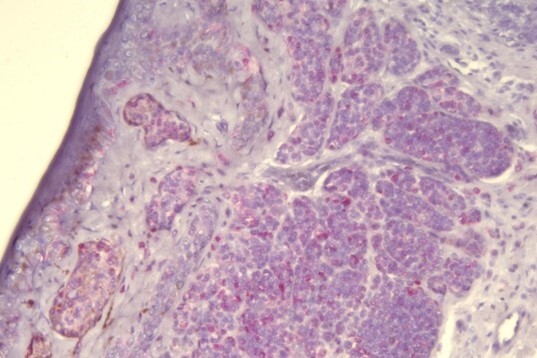

Optimization is a trial-and-error phase – tweaking protocols to get the best staining results. This helps fine-tune specificity and signal strength.

Think of validation as the ultimate test drive. It confirms that a test or stain is specific, accurate, and reproducible – giving you confidence that every time you run it, you get reliable results. Before using any test on patient samples, it must be validated.

Already have a validated test but need to make a tweak? That’s where verification comes in. It ensures that any changes still meet staining quality expectations.